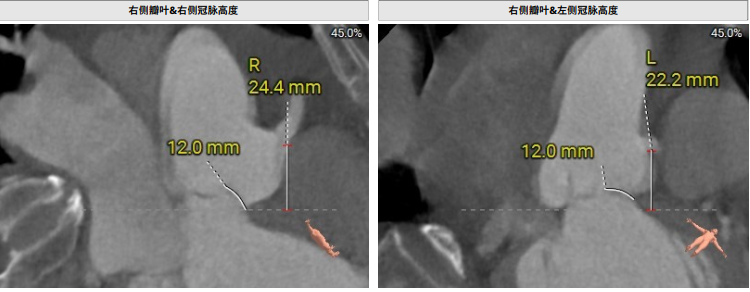

术前影像评估提示,患者主动脉瓣为三叶瓣结构,瓣叶增厚,三个瓣窦分布较为均匀,无明显钙化。主动脉瓣环直径约28.8mm,左室流出道直径30.5mm,STJ直径33.9mm,升主动脉直径34.6mm。冠脉开口高度充足(左冠22.2mm,右冠24.4 mm),冠脉走行良好,无钙化,梗阻风险低。入路角度方面,左室-主动脉夹角为138°。

上下滑动查看更多照片